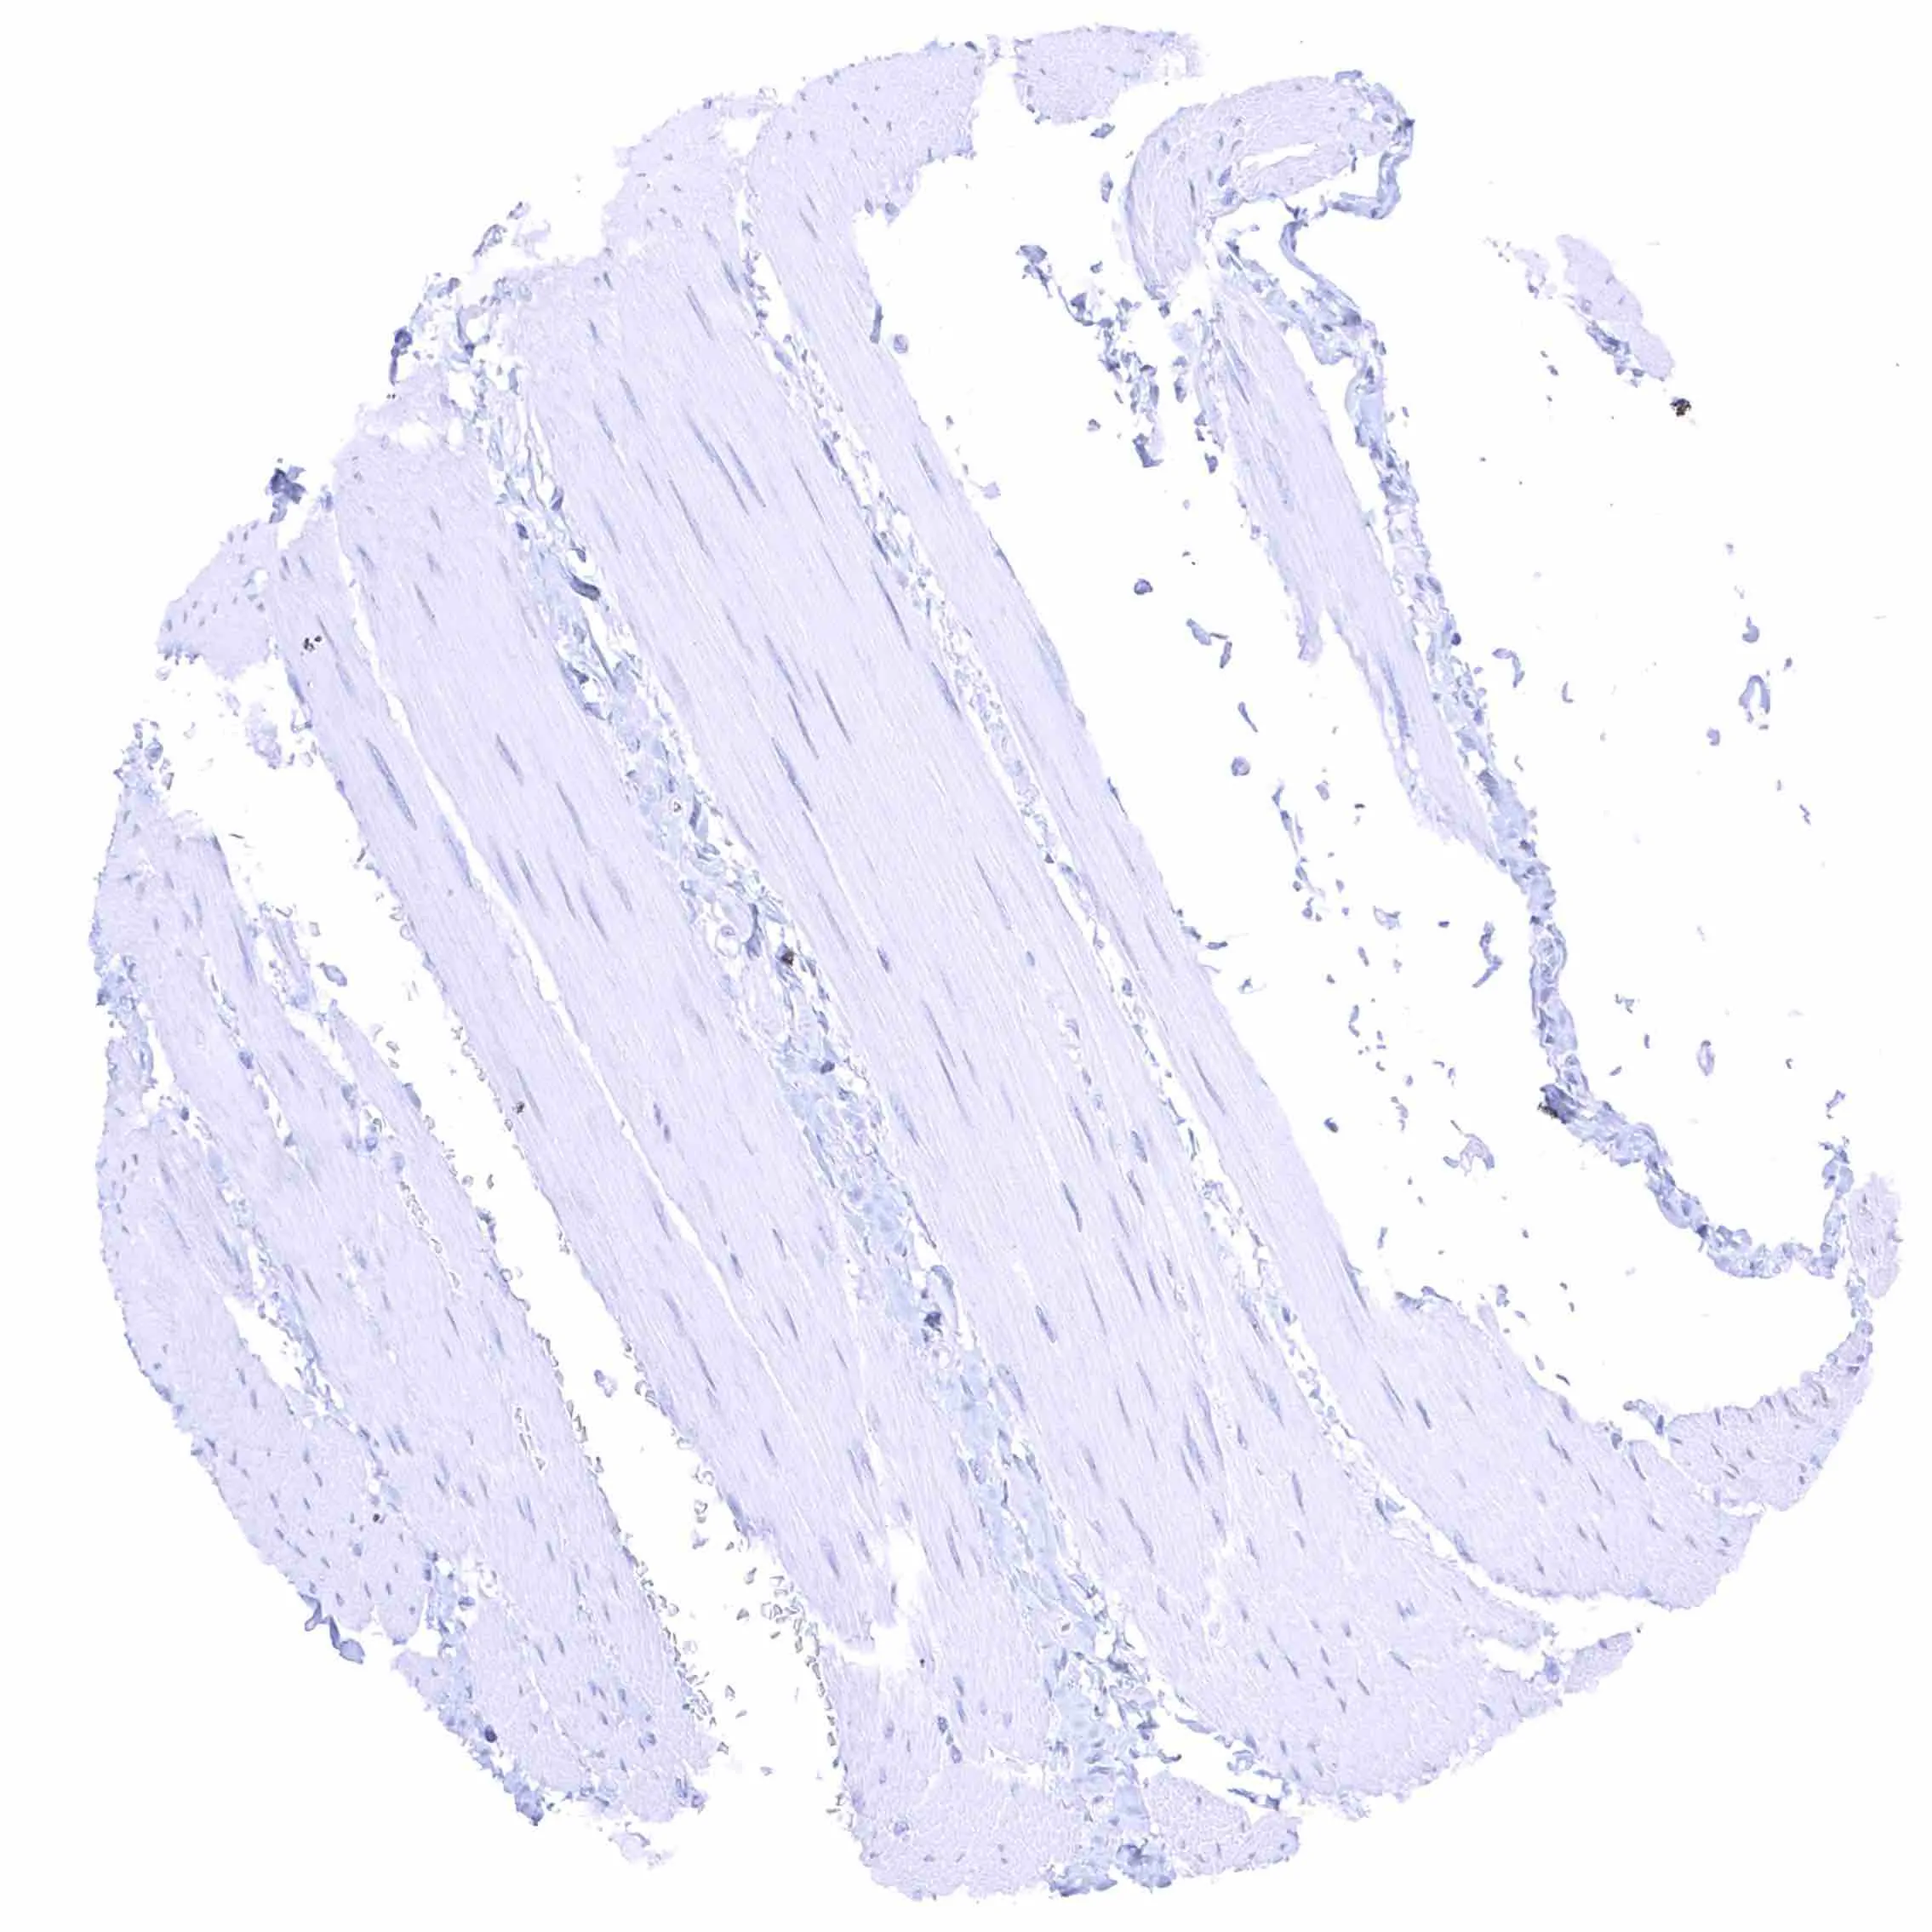

Skeletal muscle